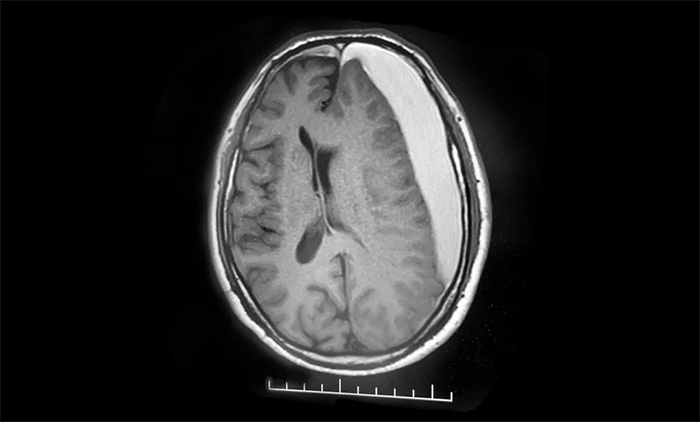

患者为老年男性。2023年12月25日中午突发言语不清,无流涎,无吞咽困难,无意识不清,当时未重视。两天后,病情加重,突发右侧肢体活动不利,摔倒,伴头晕不适,无视物模糊,无天旋地转,无恶心呕吐,无四肢麻木。经磁共振检查,诊断为左侧额颞顶部及右侧额部慢性硬膜下血肿。

▲ 左侧额颞顶部及右侧额部慢性硬膜下血肿,并挤压脑组织导致中线右偏